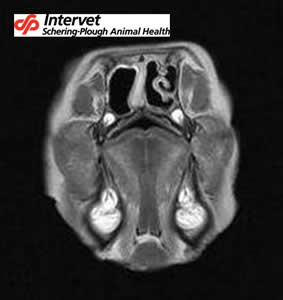

D’autres méthodes existent mais sont inutilisables en routine (Rhinoscopie, IRM, scanner…) : elles illustrent cependant bien les dégâts faits par la Rhinite Atrophique :

![]() |

Examen IRM du porc de la photo précédente : noter l’aplatissement dissymétrique de la cavité nasale, la disparition complète du cornet nasal dorsal gauche, ainsi que des volutes nasales gauche et ventrale droite. La cloison est également nettement déviée. |